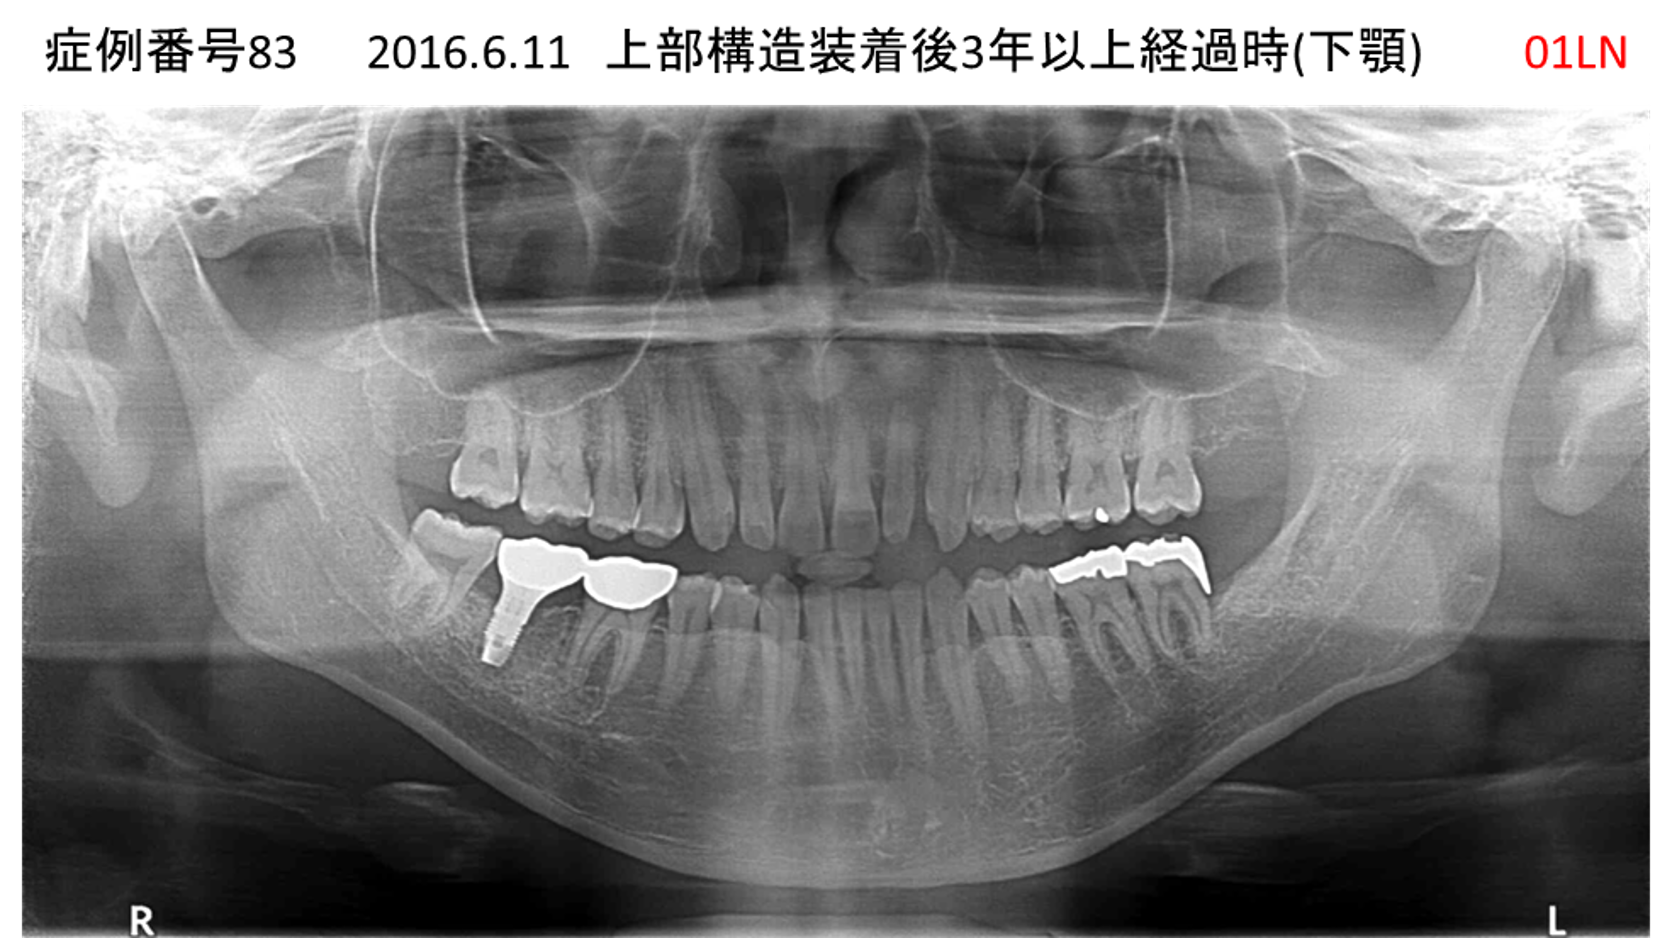

奥歯で噛めない患者様のインプラント症例

| 治療名称 |

インプラント |

| 治療費用 |

365万円+税 |

| 治療期間 |

5か月 |

| 患者さんの症状(主訴) |

奥歯で噛めない。上の前歯が揺れてきた。 |

| 治療内容 |

抜歯即時インプラント |

| 治療結果 |

食事に困らない。見た目がとても良くなった。 |

| 治療の注意点(リスク/副作用) |

インプラントが壊れたら再治療が必要 |